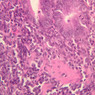

In lymphatic nodules and nodes the term primary nodule refers to a nodule of homogeneously, tightly packed small lymphocytes. When lymphatic nodules have germinal centers they are called secondary nodules. A germinal center contains lighter staining, "B" lymphocyte precursors. Mitotic figures should be easily spotted in the core of the nodule. Compare these cells with the mass of small more differentiated lymphocytes that surround the germinal center. Some of these lymphocytes are cytokine producing T-Helper cells that are stimulating the proliferation of the lymphoblasts.

6 Secondary Lymphoid Nodule (none) H&E b20 lymphoid nodule appendix 10x labeled.jpgB20, Appendix, 10x

7 Germinal Center GC H&E b20 lymphoid nodule appendix 10x labeled.jpgB20, Appendix, 10x

8 Corona C H&E b20 lymphoid nodule appendix 10x labeled.jpgB20, Appendix, 10x

9 B Lymphocyte Precursor Bp H&E b20 lymphoid nodule appendix 40x labeled.jpgB20, Appendix, 40x

10 Mitotic Figures MF H&E b20 lymphoid nodule appendix 40x labeled.jpgB20, Appendix, 40x

11 Differentiated Lymphocyte DL H&E b20 lymphoid nodule appendix 40x labeled.jpgB20, Appendix, 40x